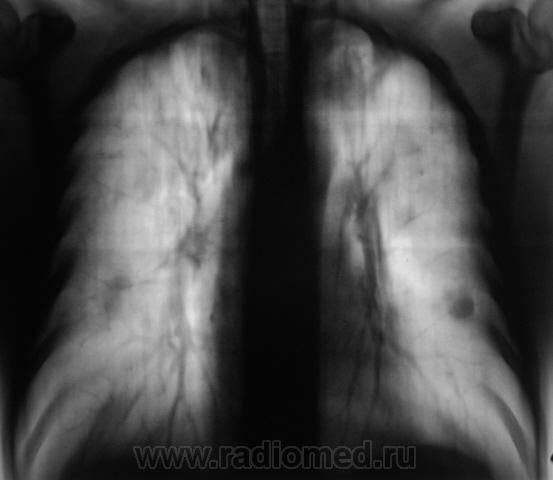

2008 г.

Нужно дифференцировать, исход диссеменированного туберкулёза ( в 2008г.) в множественные туберкулёмы в 2010г, и MTS в лёгкие с некоторой положительной димамикой, возможно на фоне проведённой химеотерапии (нужен анамнез!).

"Палка" была обнаружена, и в 2008 и 2009 гг неоднократно.